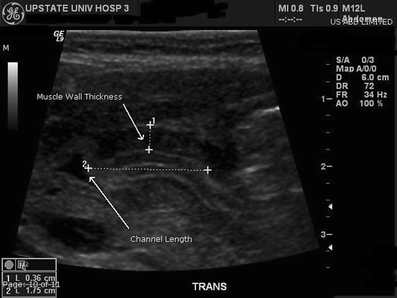

A 22-day-old healthy appearing male infant presented with persistent vomiting after feeding with onset shortly after birth. This is the father’s second child and the mother’s first. Switching formulas had been unsuccessful. Abdominal X-ray (AXR) revealed a dilated air-filled stomach with a nonspecific bowel gas pattern (Fig. 1). Ultrasound (US) demonstrated a thick and elongated pylorus, confirming the diagnosis (Figs. 2 and 3).

Radiographic signs of pyloric stenosis include gastric distension with air, a maximal gastric diameter of 7 cm or greater, and thick walled gastric antrum [3]. Abdominal US confirms the diagnosis by illustrating the increased length and thickness of the pyloric muscle.